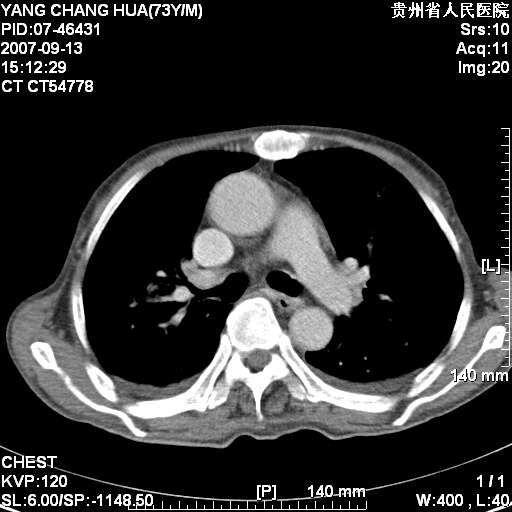

标题: CT9726:M73Y,患者因吞咽困难及腹痛半月入院!全身浅表淋巴结 [打印本页]

图像没有传全。肺部为感染性病灶;肺囊肿;双侧胸腔积液;肝脾肿大;腹水。

双肺部为感染性病灶.双侧胸腔积液;肝脾肿大;腹水.

双肺部为感染性病灶.双侧胸腔积液;肝脾肿大;脾脏密度不均,不除外脾侵润?腹水.

双肺点片状影,以双上肺改变明显.双侧胸腔积液.为感染性病灶,但不除外结核.

肝脾都大..

双肺散在斑片状及多发小结节状阴影,边缘模糊,双上肺野明显,双侧胸膜腔少量积液,纵隔及肺门区未见明显肿大淋巴结,肝脾肿大,脾内见多发低密度区,结合临床考虑恶性淋巴瘤(肺内表现为肺炎肺泡型),单看影像表现,肺结核不能排除。建议结合实验室检查或表浅淋巴结活检。